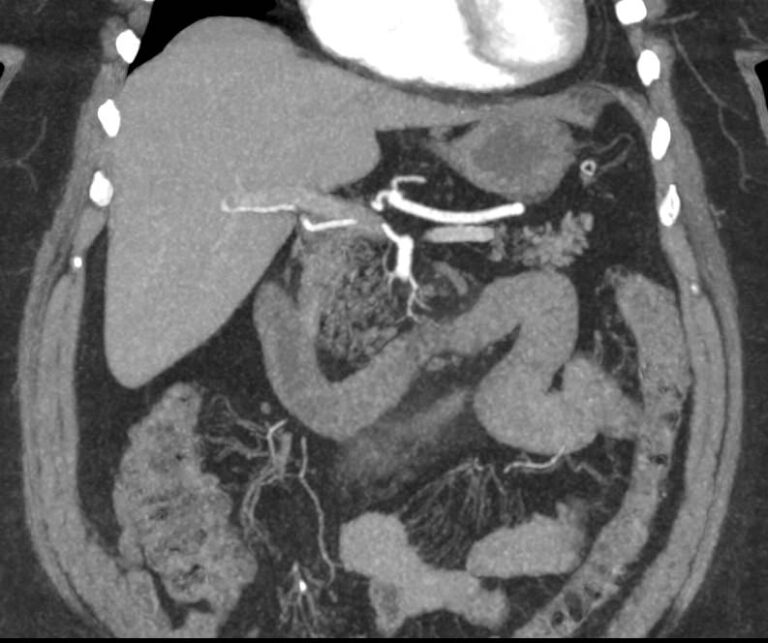

В брюшной полости и забрюшинном пространстве расположены группы лимфатических узлов, которые окружают внутренние органы (желудочные, печеночные, брыжеечные, чревные, подвздошные и др) и располагаются вдоль крупных кровеносных сосудов. Лимфоузлы относятся к периферическим органам иммунной системы человека и выполняют защитную функцию, являясь барьером для проникновения инфекций и задерживают распространение раковых клеток.

Патологические изменения регионарных лимфоузлов часто свидетельствуют о поражении того органа, от которого происходит лимфоотток. Это имеет важное значение для оценки распространенности онкологического процесса, выявления отдаленного метастатического поражения лимфатической системы, а также используется для определения тактики лечения. Кроме того, патология лимфатических узлов может говорить о развитии гемобластозов и лимфопролиферативных заболеваний крови.

Компьютерная томография позволяет детально визуализировать структуру лимфатических узлов, выявить ее неоднородность, гиперплазию, определить деформацию контуров, появление инфильтрации окружающих тканей с образованием пакетов и конгломератов лимфоузлов.

С целью повышения контрастности изображений, выявления патологических изменений в лимфоузлах дополнительно внутривенно вводится рентгеноконтрастное вещество на основе йода. Контраст накапливается в патологических очагах и под воздействием рентгеновских лучей обусловливает их яркое изображение на фоне неизмененной ткани. Контрастирование значительно повышает диагностическую ценность исследования и помогает выявлять многие серьезные заболевания на начальных этапах.